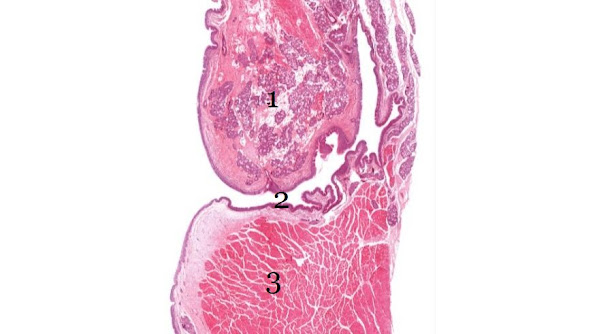

1. Falso pliegue vocal (o ventricular): Tiene como función principal proteger las cuerdas vocales verdaderas.2. Ventrículo laríngeo: Un divertículo lateral que separa los pliegues falsos arriba de las cuerdas vocales verdaderas abajo.3. Cuerda vocal verdadera: Son responsables de la producción de la voz.

7. Ligamento Vocal - Banda gruesa de tejido conectivo dentro de la lámina propia cerca de la superficie de la cuerda vocal.Epitelio escamoso estratificado no queratinizado: Cubre esta región de la laringe porque está sujeta a estrés mecánico.8. Músculo Vocal - Músculo esquelético que subyace y regula la tensión del ligamento vocal.